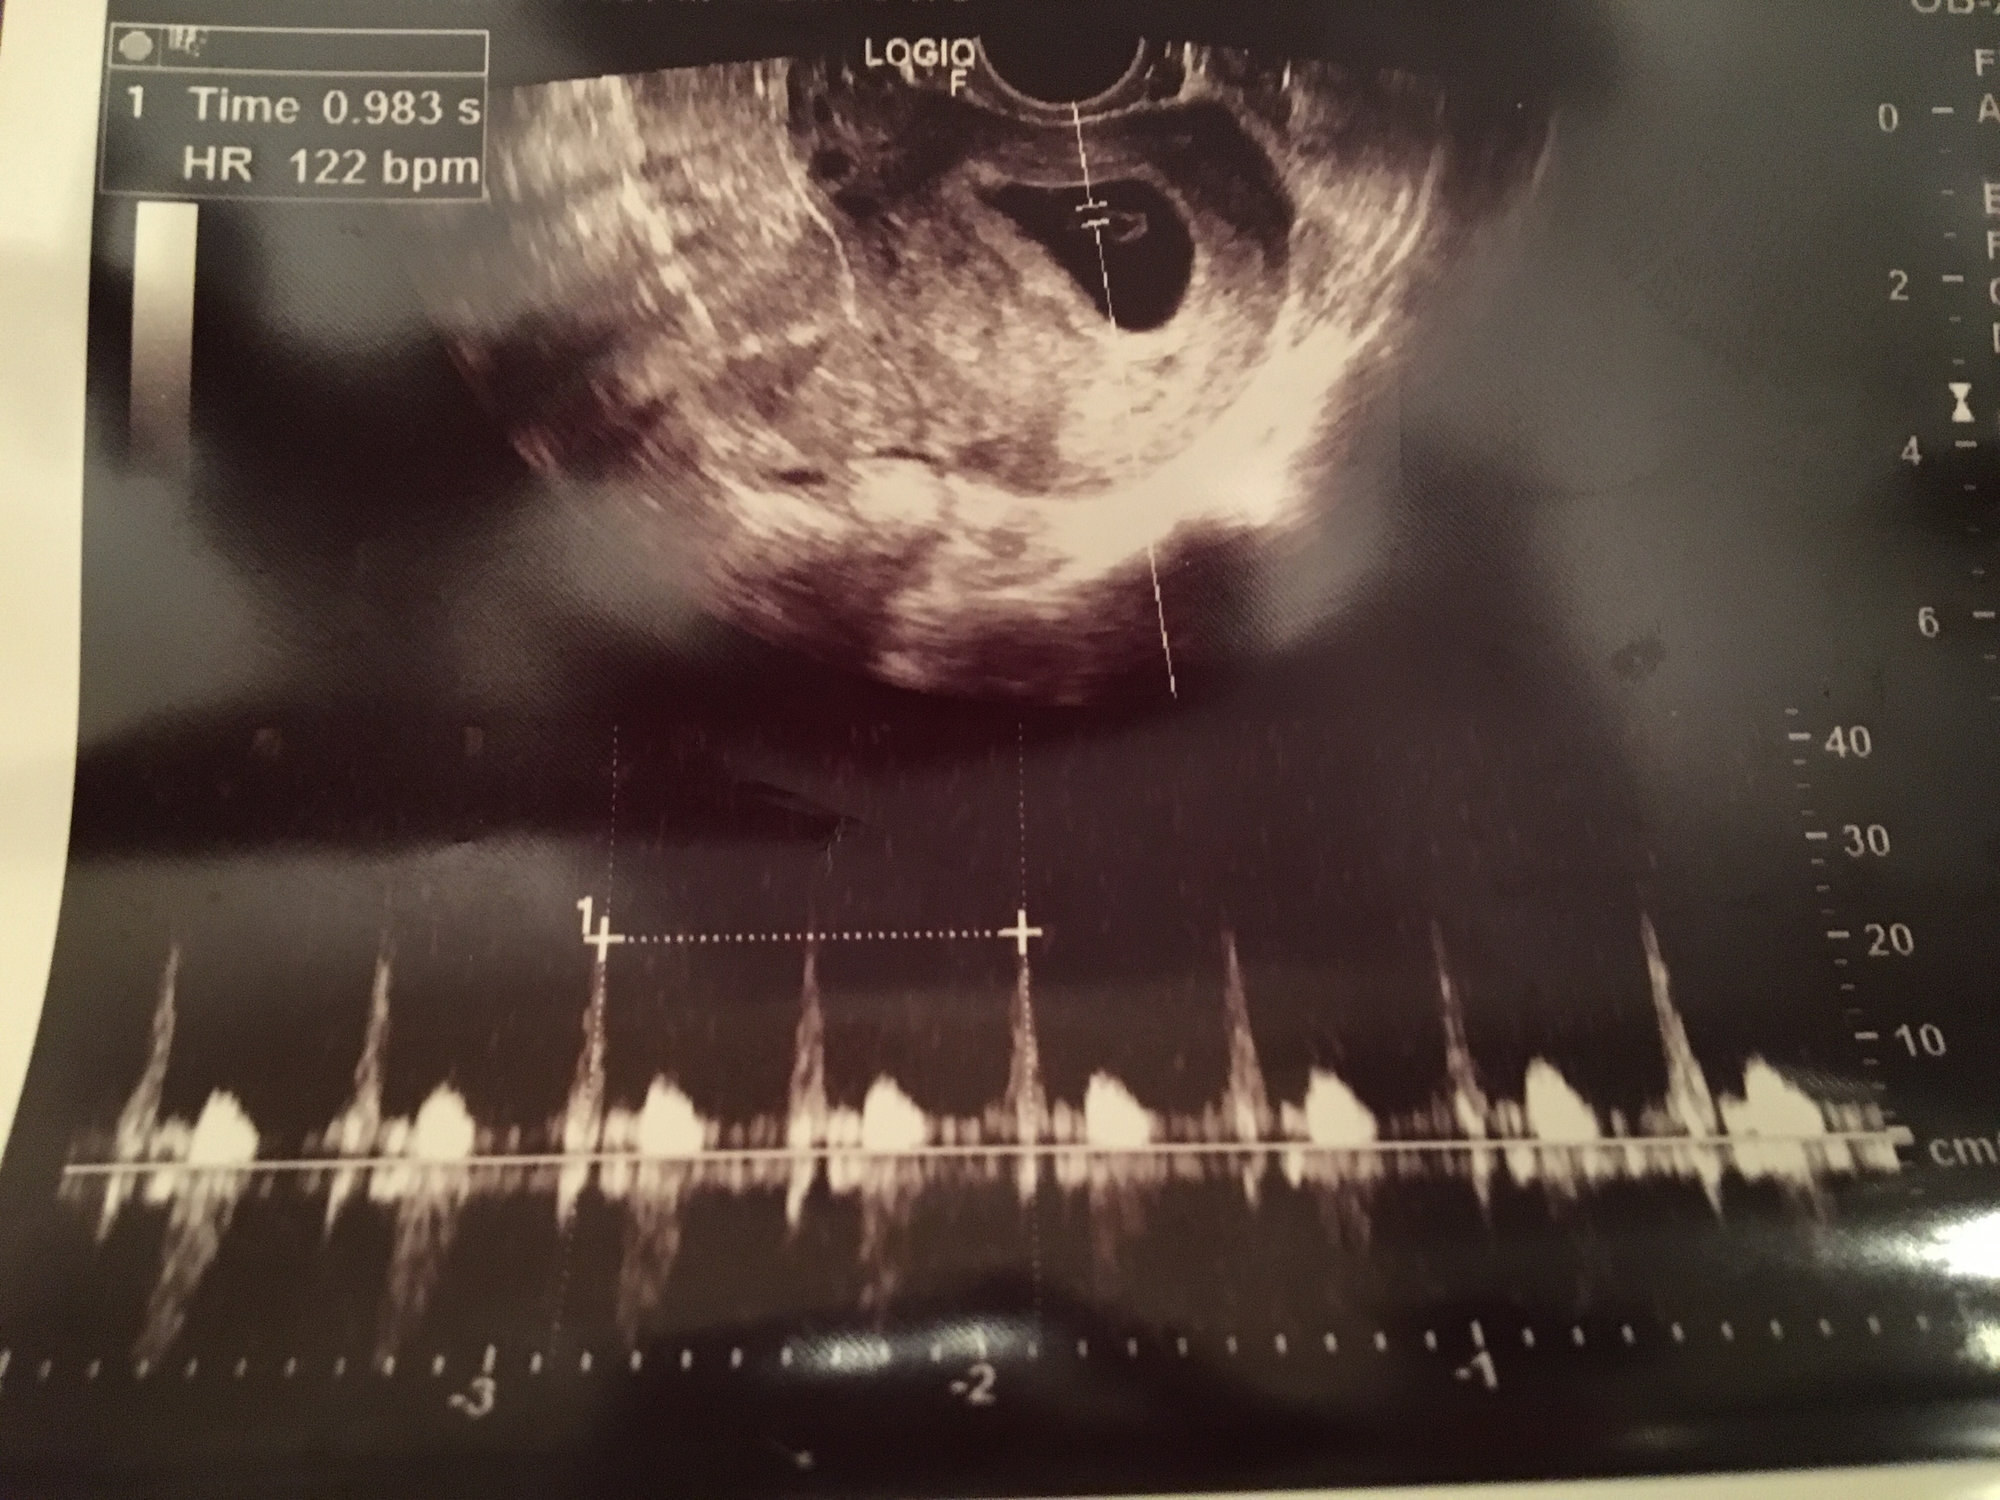

got to hear the heartbeat today too! It was such a gift to get to hear it. Heart rate was 122 and so far everything looks good. He said if I can make it two more weeks my loss chance goes down significantly. Next ultrasound at 8 weeks.